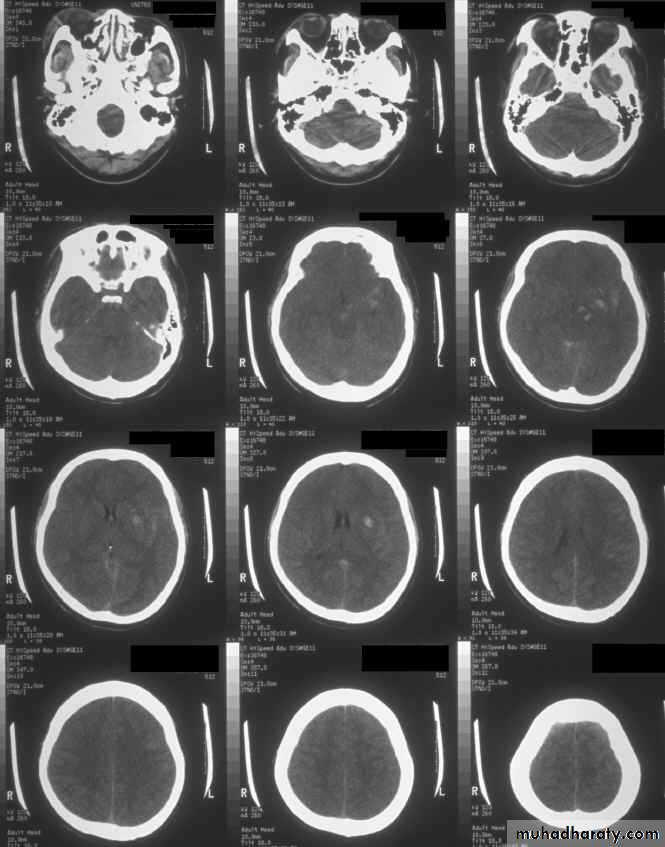

b. Subdural Haematoma

They are the most common intracranial mass lesions resulting from head trauma.

They are classified depending on how long they take to present clinically following the injury into:

Acute Subdural Haematoma: less than 3 days

Subacute Subdural Haematoma: 4-21 days

Chronic Subdural Haematoma more than 21 days.

Acute Subdural Haematoma

Usually due to MORE SEVER high velocity trauma and thus associated with a poorer outcome.

Clinical Picture: patient will present with a picture similar to that of an extradural haematoma, but there is persistent loss of consciousness with no lucid interval.

Ct scan will show a concave hyperdence collection because blood follows the subdural space over the convexity of the brain.

Acute Subdural Haematoma are rapidly evolving lesions and early evacuation via craniotomy is mandatory.

Chronic Subdural Haematoma

Most common in infants and in adults over 60 years of age secondary to SLIGHT blow to the head which may pass unnoticed.

Source of bleeding (haematoma): usually from bridging veins as they pass to the venous sinuses.

The patients present with progressive neurological deficits more than 3 weeks after the trauma.

The initial head injury is often completely forgotten.

CT scan: the acute clotted blood is initially appears white (hyperdence), but as it liquefies, it slowly becomes black (hypodense).

They should be drained if they continue to enlarge.

They are evacuated by drilling burrholes over the collection and washing it out with warmed saline.